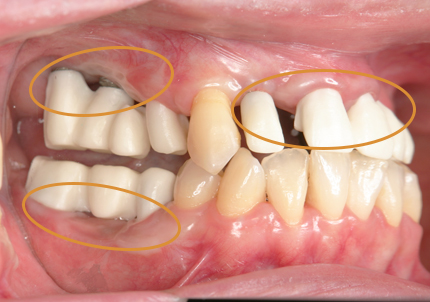

16.下顎インプラント補綴治療終了(2017年4月8日)

23.口腔内写真(2024年6月26日)

25.初診より18年経過(2024年6月26日)